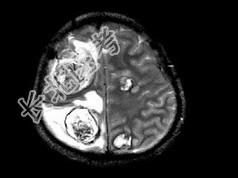

- 单项选择题男,22岁, 耳后见一直径约2cm黑痣,表现有溃烂, 近期增大明显,头痛1周, 伴咳嗽、胸闷,行头颅CT及MRI检查见颅内多发病灶, 最可能的诊断为 ( )

A、黑色素瘤脑转移